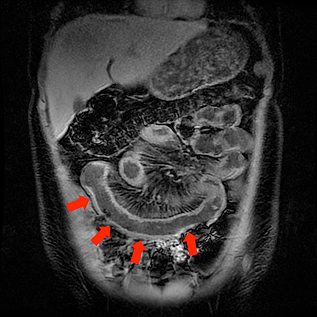

Patient with Crohn’s disease showing multiple=